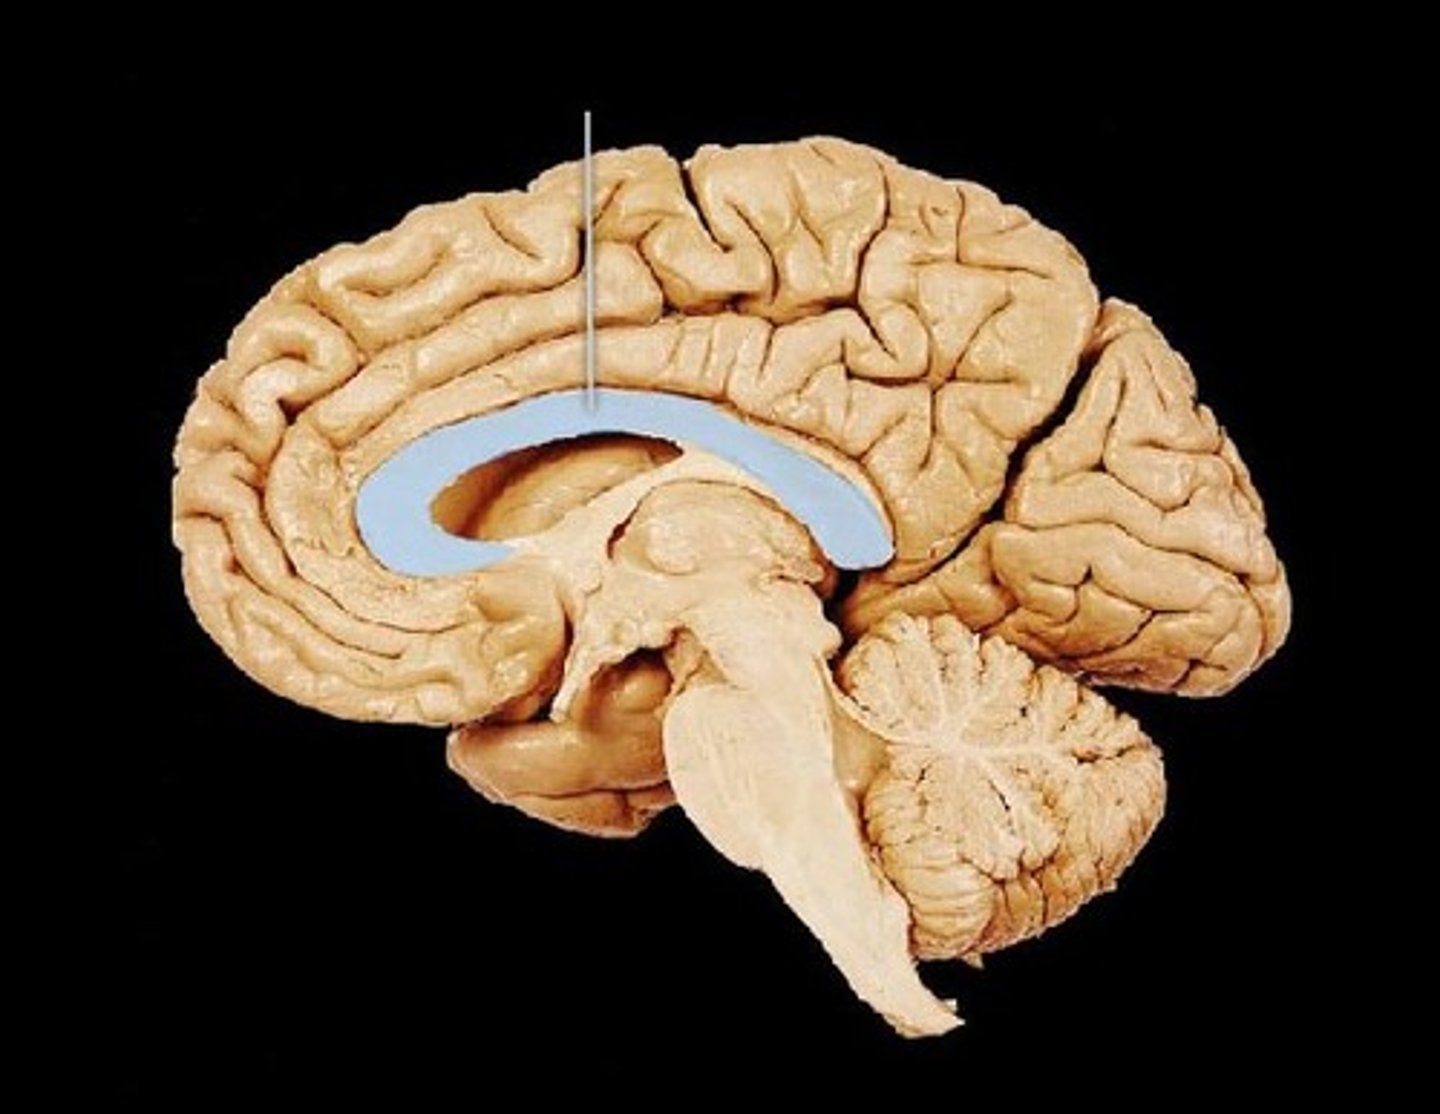

MIdsagittal View of brain

Lateral Ventricle

Third Ventricle

Cerebral Aqueduct

Forth Ventricle

Corpus Callosum

Fornix

Thalamus

Pineal Gland

Superior Colliculi

Inferior Colliculi

Midbrain

Hypothalamus

Cerebral Cortex Gray Matter (nerve cell bodies)

White Matter (myelinated nerve fibers)